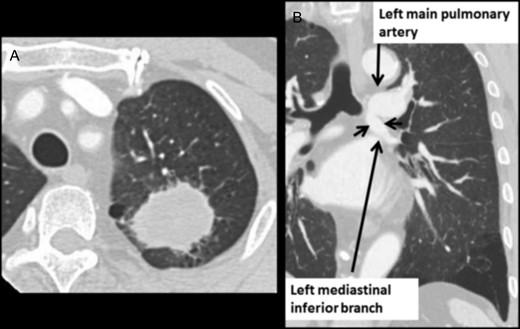

A 65-year-old man with an abnormal shadow on his chest X-ray was referred to our department. Computed tomography (CT) revealed a solid mass with a 39-mm maximum diameter in the left upper lobe (Fig. 1A). He was diagnosed with lung adenocarcinoma (c-T2a N0 M0, c-stage IB according to the seventh edition of the Lung Cancer Classification). Abnormal mediastinal inferior lobar branch of the PA was not detected preoperatively. Retrospectively, a thin-section CT scan revealed that the mediastinal anatomical variation was that the first trunk of the PA flowed into the lingular and basal segments (Fig. 1B).

(A) Chest CT shows lung mass in the left upper lobe. (B) Chest contrast-enhanced CT shows the mediastinal anomalous inferior lobar branch.